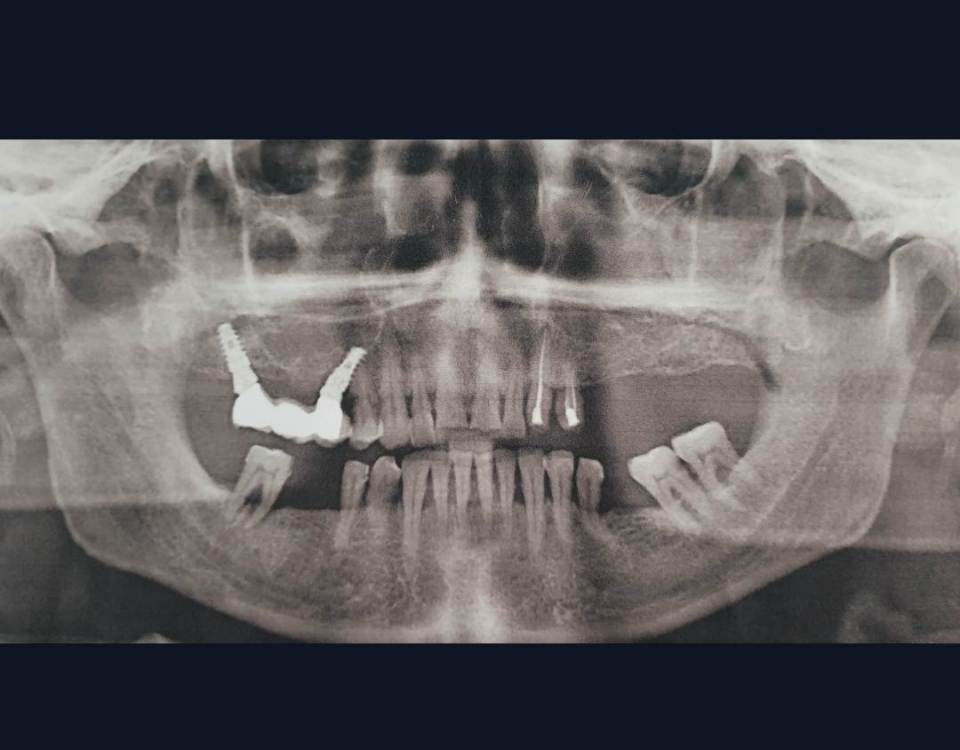

Карен Аванесов Опубликовано 10 мая, 2021 Автор Поделиться Опубликовано 10 мая, 2021 17 минут назад, It'sGeorgy сказал: Если есть фото и снимок после протезирования, добавьте пожалуйста. Правильно ли я понимаю, что у дистального имплантата мультиюнитом выход шахты будет как раз посередине 1.7? Что думаете о таком концепте? (взял со Штраумянского недавнего онлайн-форума) Фото покажу позже. Да, возможно так и будет. Очень здорово что Вы смотрите такие онлайн-форумы, наверно поучительно. Моей работе на слайде 7 лет, хирургия и ортопедия моя, зуботехническая работа такая как есть, фиксация цементная, на дистальном имплантате индивидуальный титановый абатмент, тем не менее нет каких либо проблем. Близкое расположение имплантатов, в данном случае рентгенологический артефакт. Пациентке было с чем сравнивать ощущения, слева делал открытый синуслифтинг, гуманный подход он лучше для пациента и оператора, на мой взгляд. 2 1 2 Ссылка на комментарий

Aquarius Опубликовано 10 мая, 2021 Поделиться Опубликовано 10 мая, 2021 Круто. Почему у настолько близко расположенных друг к другу имплантов не уходит кость? По плоскости смещены?? Ссылка на комментарий

Карен Аванесов Опубликовано 10 мая, 2021 Автор Поделиться Опубликовано 10 мая, 2021 2 часа назад, Aquarius сказал: Круто. Почему у настолько близко расположенных друг к другу имплантов не уходит кость? По плоскости смещены?? Все же искажение сильное, но делал так, с любовью делал, сначала одномоментно в 1.4 зуб, через несколько месяцев 1.5, без сильного торка, что бы не сдавливать костные структуры и мягкотканую аугментацию сделал. Ссылка на комментарий

rustam. Опубликовано 4 февраля, 2022 Поделиться Опубликовано 4 февраля, 2022 Эту имплантацию делал 2014 году, в то время не было опыта делать синуслифтинг и по этому я так обошел пазуху имплантами Ссылка на комментарий